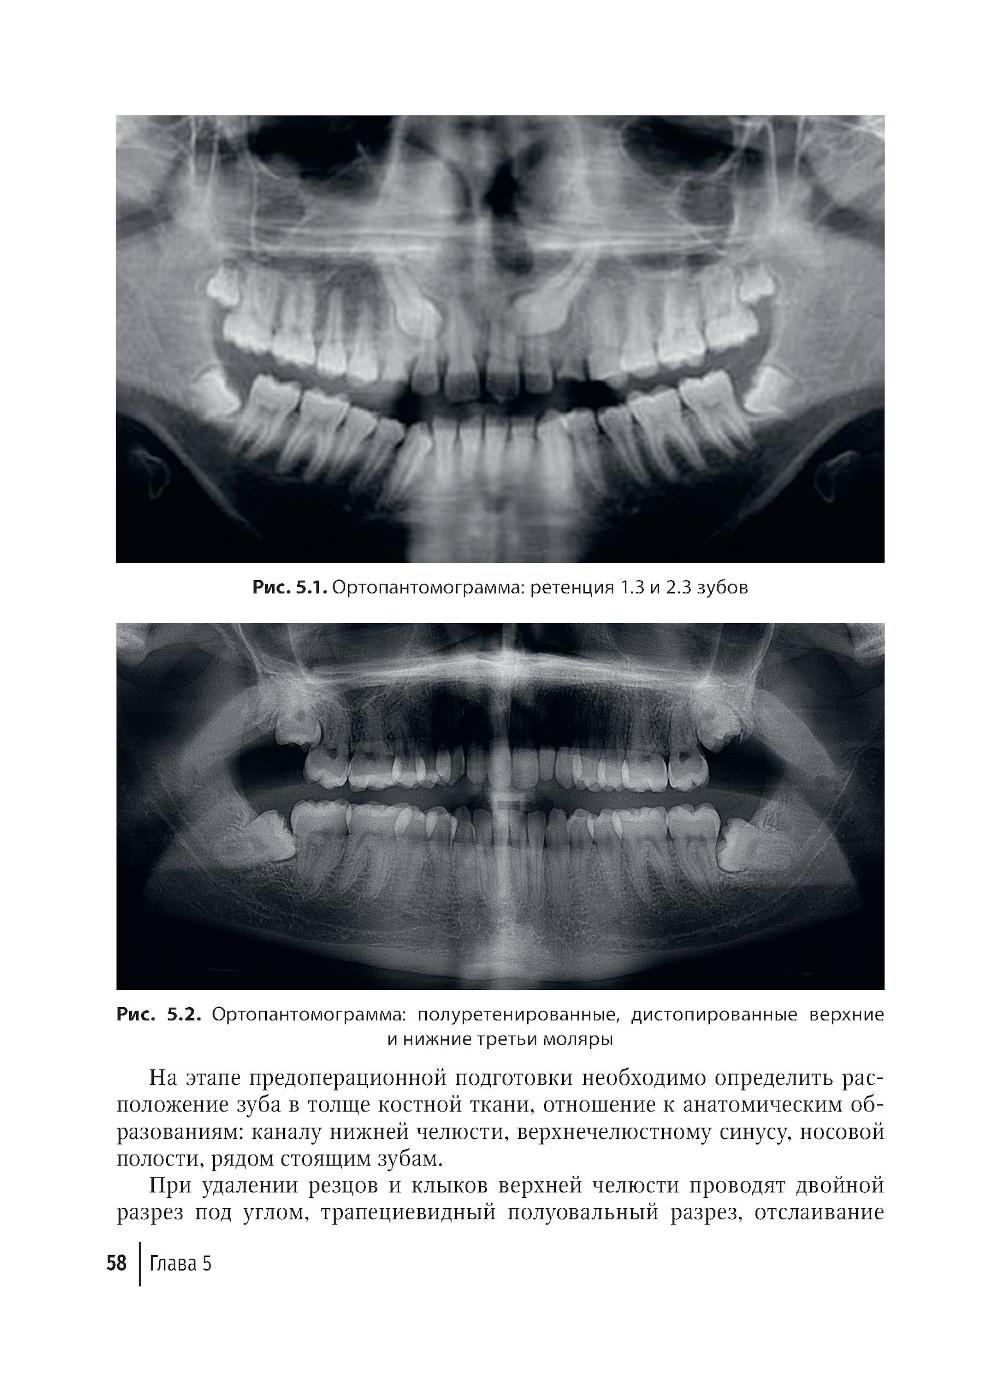

В руководстве представлены основные современные группы остеопластических материалов, применяемых в хирургии полости рта, описаны их характеристики и свойства. Приведены клинические примеры применения остеопластических материалов при альвеолосохраняющих методах удаления зубов с целью сохранения объема костной ткани, в реконструктивной хирургической стоматологии при удалении ретенированных зубов, операциях цистэктомии для заполнения костных полостей. Продемонстрирована значимость применения остеопластических материалов на этапах дентальной имплантации, при проведении субантральной аугментации, аугментации костного гребня при проведении операции для увеличения объема костной ткани. Даны примеры использования остеопластических материалов и мембран при проведении направленной костной регенерации при лечении заболеваний пародонта, а также при лечении осложнений дентальной имплантации. Издание рассчитано на практикующих врачей - стоматологов-хирургов, ординаторов, аспирантов, а также студентов высших медицинских учебных заведений.